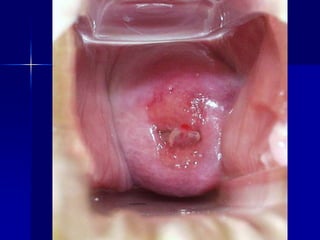

5. Гістероскопія застосовується для виявлення наявності підслизових

фіброматозних вузлів, стану ендометрія, у деяких випадках –

гістеросальпінгографія. Перевагою гістероскопії є можливість

одночасної біопсії ендометрія, видалення поліпів і субмукозних

вузлів, абляції і резекції ендометрія.